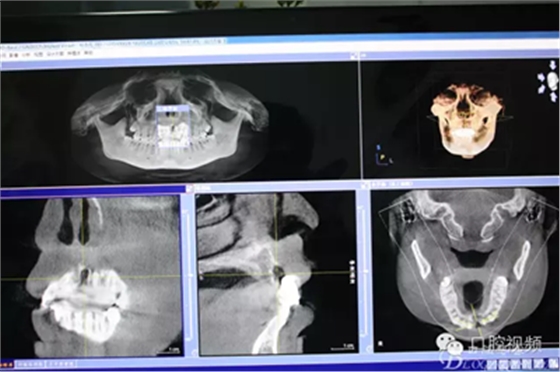

圖3.CBCT影像檢查:21唇側(cè)、腭側(cè)骨壁完全破壞